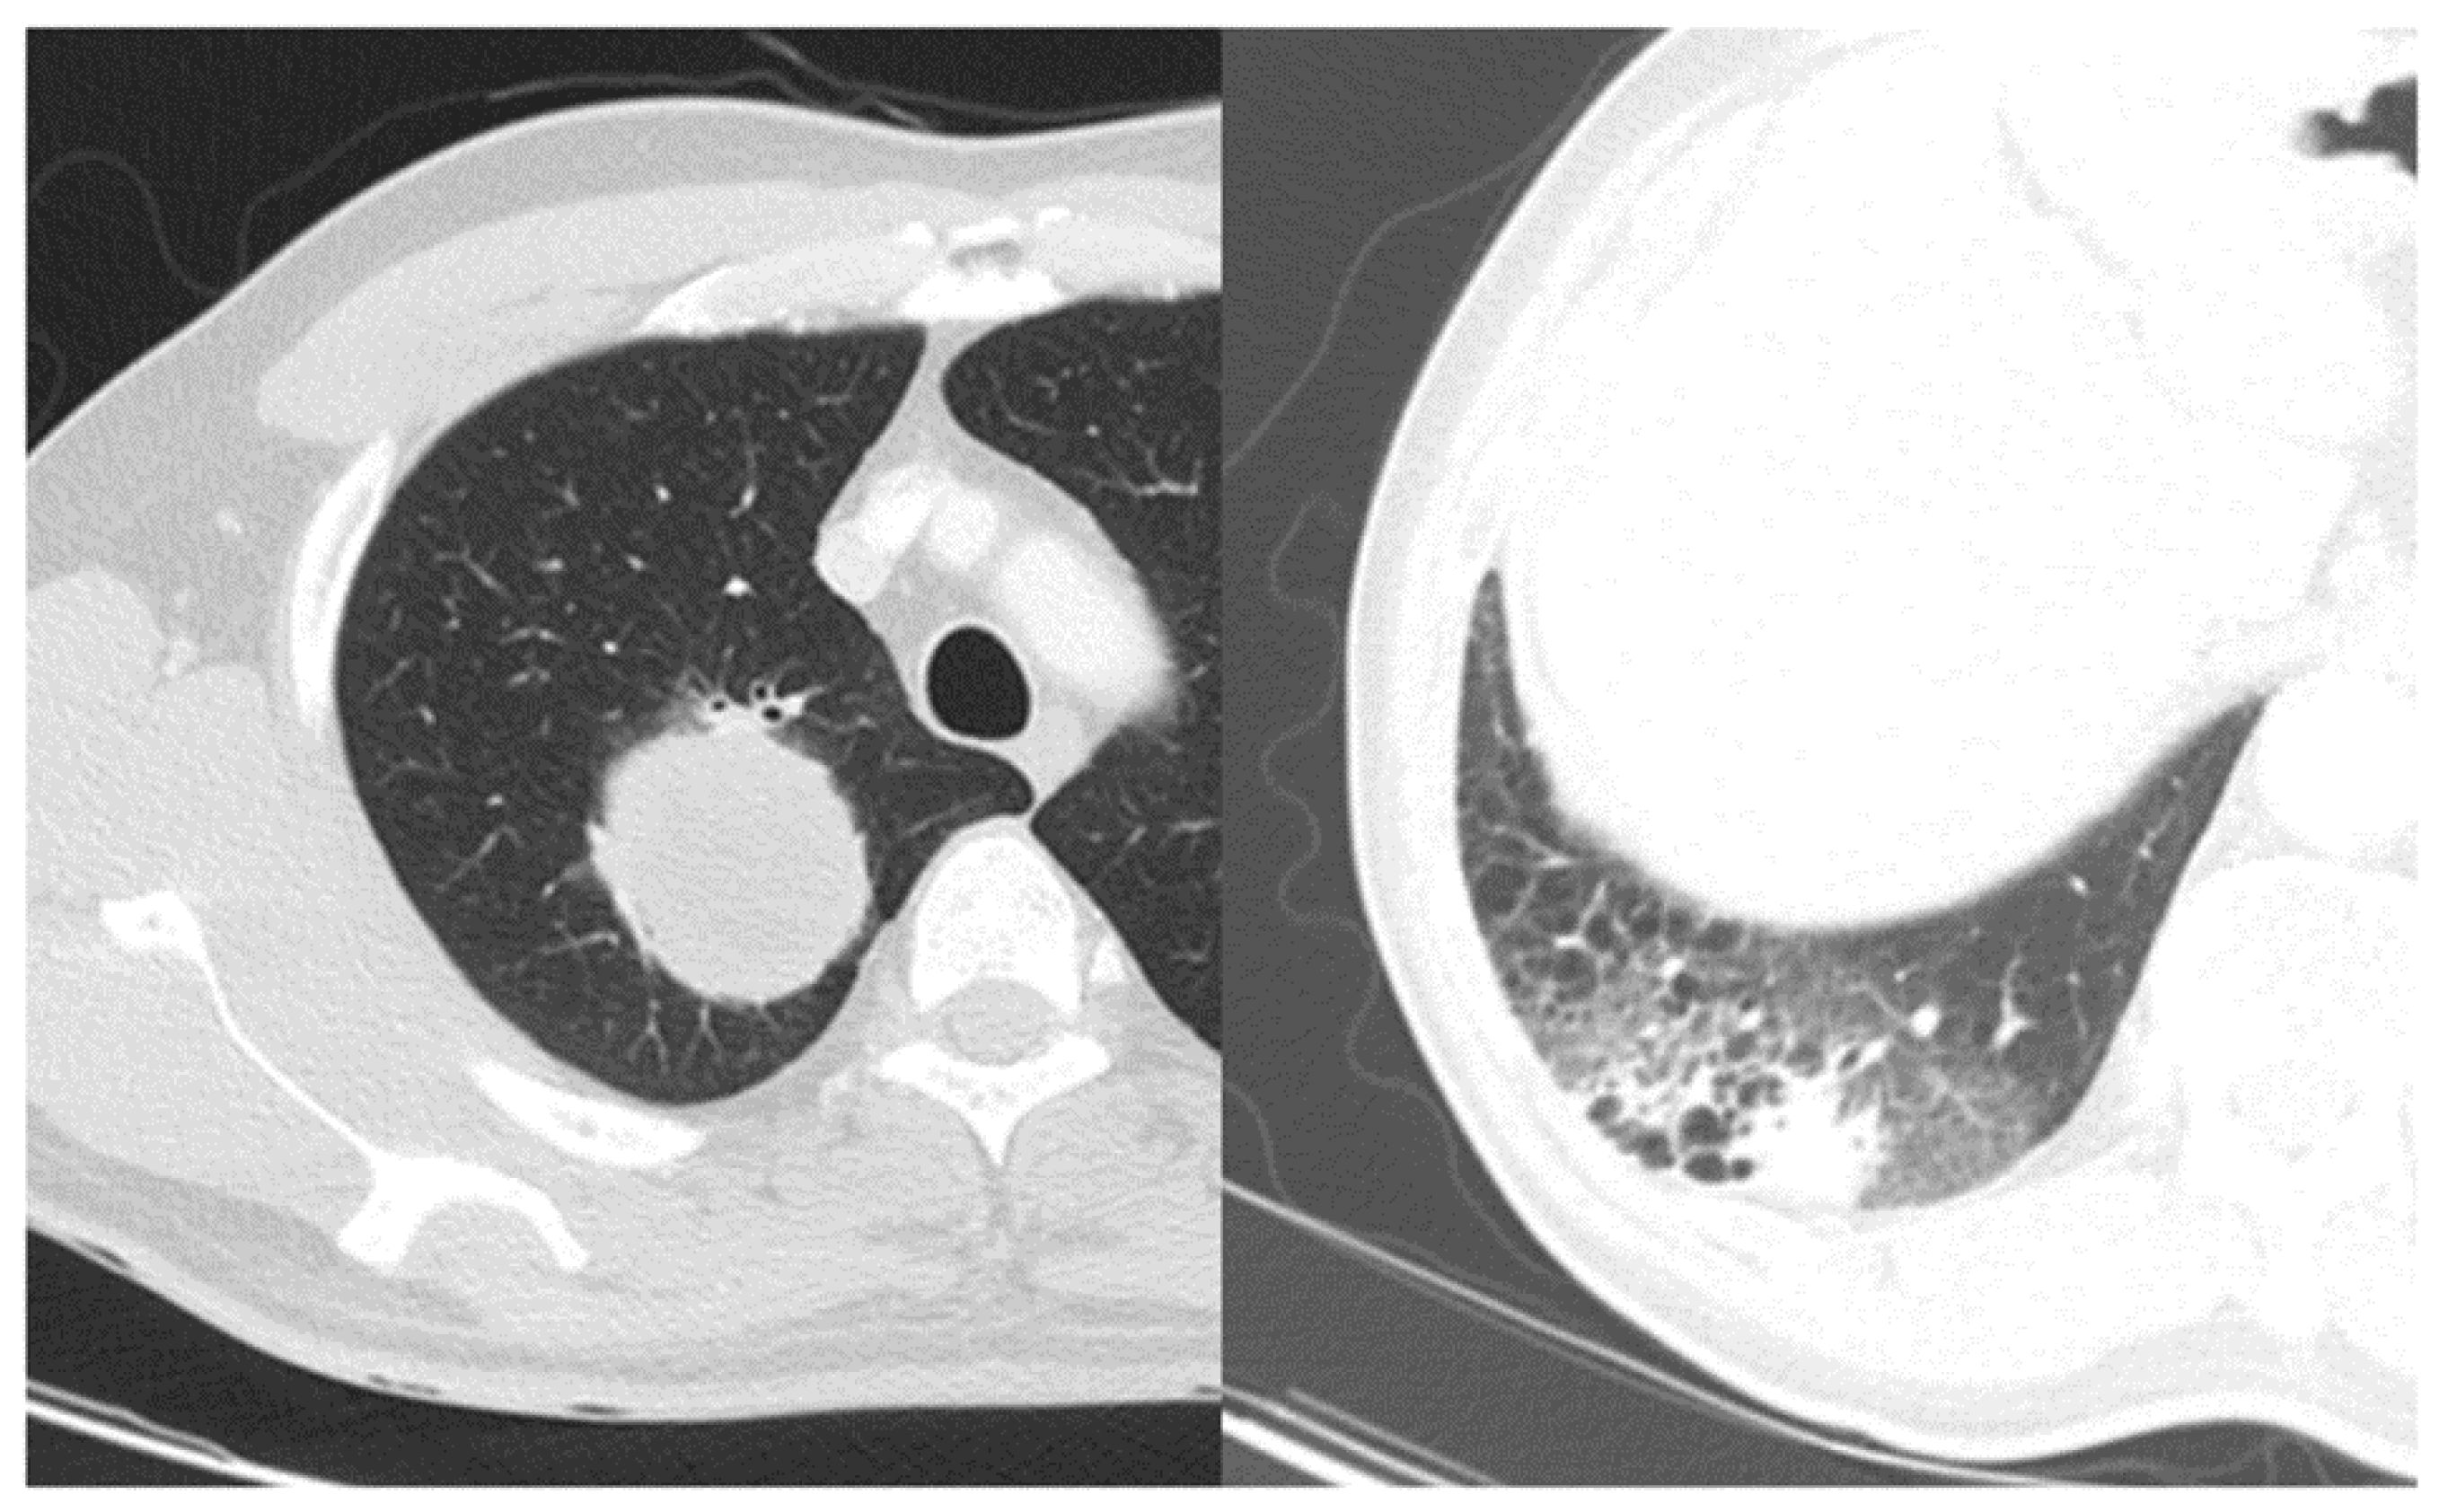

Figure 2. Comparison of lung adenocarcinoma with well-defined smooth margin (left) and ill-defined irregular margin (right).